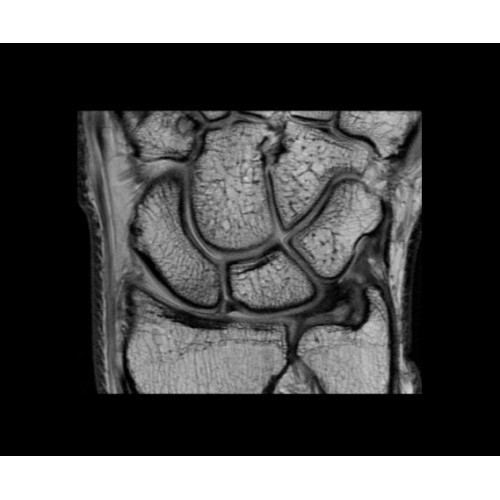

SIGNA PET/MR 3.0T — это гибридная система, в которой совмещаются две принципиально разные технологии — магнитно-резонансную томографию (МРТ) и позитронно-эмиссионную томографию (ПЭТ). Система отличающийся высокой чувствительностью и эффективностью и предназначена для диагностики в области онкологии, неврологии, кардио-васкулярных исследований, исследований воспалительных процессов.

Компания GE Healthcare представляет революционную, полностью интегрированную систему SIGNA PET/MR1, в которой сочетаются времяпролетная технология (TOF) и возможности напряженности магнитного поля 3.0 Тл. Мы поможем вам поднять исследования на более высокий уровень. SIGNA PET/MR позволяет достичь впечатляющей точности и скорости исследований, а благодаря новейшей технологии реконструкции Q.Clear2 качество изображений улучшается в два раза. Кроме того, в систему включен полный набор клинических приложений и гибких катушек для проведения любых видов исследования, открывая для вас возможности визуализации, о которых вы даже не догадывались.

• Приложения для коррекции артефактов движения — используйте наиболее широкий набор инструментов, таких как PROPELLER, PROMO и навигаторы Pencil Beam, позволяющих снизить влияние непроизвольных или физиологических движений на качество изображений.

Стандартный пакет приложений SIGNA Works позволит вам достичь желаемых результатов в клинической практике благодаря набору высокоэффективных средств визуализации. Программные приложения, входящие в состав данных клинических пакетов, включают широкий спектр контрастов, функции обработки 2D- и 3D-данных, а также возможность коррекции артефактов движения. SIGNA Works предоставляет набор инструментов, необходимых для проведения эффективного клинического исследования.